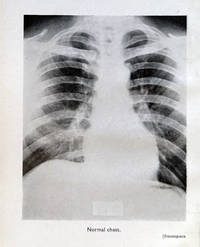

Edinburgh:: E. & S. Livingston, 1946., 1946. Small 8vo. xvi, 277, [3] pp. 124 figures, index. Original dark green blind- and gilt-stamped cloth. Ex-library copy, Mount Sinai Hospital, with related spine label, rubber-stamps, etc. Keers was an Irish-born physician, an expert in tuberculosis and battled with the disease both personally and in his duties.